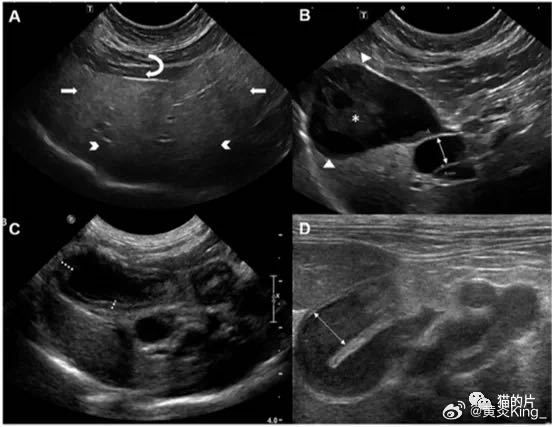

兽医文献中缺乏描述与猫胆管炎/胆管肝炎的特定炎症表型相关的超声特征的信息。相反,回顾性观察研究报道将超声特征描述为一组炎症性胆道疾病(图3)。总体而言,肝实质的超声表现是多变的、非特异性的并且可能是不显著的;因此,它不能用于可靠地排除或诊断猫的NC。Marolf等(2012)报道,胆管炎/胆管肝炎患猫可表现正常(69%,18/26)、大(27%,7/26)或小(4%,1/26)的肝脏。据报道,肝脏的回声可表现正常(39 ~ 54%)、高回声(13% ~ 38%)或低回声(8 ~ 48%)。局灶性或多灶性结节罕见(8 ~ 17%)。胆道影像学表现可能不显著(48%,11/23),也可能表现各种异常,如肝内/肝外胆管扩张、胆囊扩张、胆囊“淤泥”增多和胆囊壁或胆管壁增厚。猫的正常CBD直径是 ≤ 4 mm。正常胆囊壁厚度 < 1 mm。不论炎症表型如何,通常报道的胆道超声异常包括胆囊壁厚度增加(15 ~ 83%),CBD扩张(31 ~ 50%)和胆囊“淤泥”增加(33 ~ 38%)。

图3. 胆管炎/胆管肝炎患猫的超声图像。(A,B)8岁雌性已绝育家养短毛猫,患有中性粒细胞性胆管炎/胆囊炎和肝脏脂质沉积症。(A)肝实质弥漫性高回声(实心白色箭头)、深部超声信号过度衰减(白色V形)。相对于镰状脂肪垫(弯曲的白色箭头)肝脏呈高回声。(B)胆囊壁有轻度弥漫性增厚(实心白色箭头)。胆囊腔内有小叶、无定形回声物质(白色星号)。胆囊管扩张(双头白色箭头)。进行了超声引导的PUC,细菌培养鉴定出肠球菌生长。该猫通过住院支持性护理、食道饲管补充营养支持和药敏试验指导抗生素治疗成功。(C,D)13岁雌性已绝育家养短猫猫,患有与扁形吸虫相关的慢性胆管炎/胆囊炎。(C)胆囊壁呈弥漫性增厚、高回声,测量高达2 mm(虚线白线)。管腔内无回声物质。(D)胆囊管严重弥漫性扩张(双头白色箭头),未发现CBD(9.1 mm)阻塞。该猫室内饲养,可通过围栏进出。基线生化参数异常包括肝酶活性升高,AST[320 U/L;参考区间(RI) 13 ~ 43 U/L],ALT(222 U/L;RI 32 ~ 83 U/L),ALP(433 U/L;RI 11 ~ 60 U/L),高胆红素血症(6.3mg/dL;RI 0.1 ~ 0.4mg/dL),低白蛋白血症(1.8mg/dL;RI 2.2 ~ 3.4g/dL)和高球蛋白血症(7.1g/dL;RI 3.4 ~ 5.3g/dL)。通过粪便沉降鉴定了扁形吸虫卵。这只猫住院了3天,进行支持治疗与吡喹酮(20mg/kg,SC,q24h,连续 4 天)。Images courtesy of Eric T. Hostnik DVM, MS, DACVR-DI, DACVR-EDI (Ohio State University, College of Veterinary Medicine) and Andrew Specht DVM, DACVIM (University of Florida, College of Veterinary Medicine).

猫EHBDO的诊断可能很困难,但对于决定猫是否需要紧急手术干预或药物治疗至关重要。超声诊断EHBDO的标准包括直径超过5 mm的CBD扩张、肝内胆管扩张和确定的明显阻塞源(如胆总管结石、胆管淤积阻塞、肿瘤)(图3)。胆囊大小不是EHBDO的可靠指标,因为它在确诊梗阻的猫中可能表现正常,在没有梗阻的情况下可能扩张。